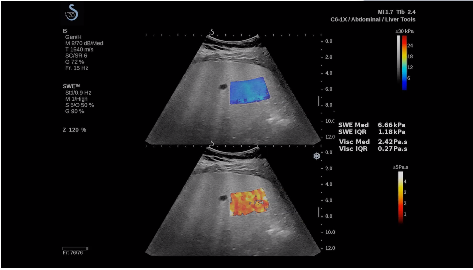

法國聲科影像(SuperSonic Imagine,SSI. Euroniex:FR0010526814)近日發(fā)表公告,宣布其研發(fā)的新一代“極速”超聲成像平臺(UltraFast Imaging),首次實(shí)現(xiàn)了肝臟的多項(xiàng)超聲定量評估新指標(biāo)同步檢測,包括:Att PLUS,SSp PLUS和Vi PLUS等,基本涵蓋肝臟相關(guān)病理變化指征的如纖維化、脂肪變、炎癥等。據(jù)悉,此多項(xiàng)新技術(shù)新將搭載于新Aixplorer系列E超系統(tǒng)。

法國聲科影像公司(SuperSonic Imagine. SA,F(xiàn)rance),2005年由三位諾貝爾獎(jiǎng)級科學(xué)家主導(dǎo)創(chuàng)立,專注于E超的開發(fā)和生產(chǎn),是目前世界上唯一可以同時(shí)應(yīng)用兩種波進(jìn)行人體檢測的系統(tǒng):縱波形成高質(zhì)量的二維組織結(jié)構(gòu)圖像,而橫波可以使醫(yī)生實(shí)時(shí)準(zhǔn)確地看到并分析組織的硬度,有效減少有創(chuàng)檢查、避免損傷。

E超相關(guān)技術(shù)已被多項(xiàng)多中心大樣本研究證實(shí)對于肝纖維化無創(chuàng)評估有重要意義,同時(shí)也可全面應(yīng)用于乳腺、甲狀腺、肝臟、前列腺、肌骨、婦科等全身各組織器官的定量評估和鑒別診斷。在慢性肝臟方面,聲科E超的肝臟相關(guān)定量診斷技術(shù)集,于2018年獲得美國FDA認(rèn)證,成為FDA歷史上首次獲批的單病種超聲全面定量解決方案。